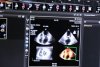

В I триместре беременности для УЗИ-диагностики тазовых и плодных структур показаны трансвагинальное и трансабдоминальное исследования, совокупность данных которых предоставляют взаимодополняющую

УЗИ в акушерстве: Воротниковое пространство и Генетический скрининг

Генетическая сонография – целевое скрининговое УЗИ, направленное на обнаружение структурных и сонографических аномалий плода, а также сонографических маркеров, которые свидетельствуют о высоком